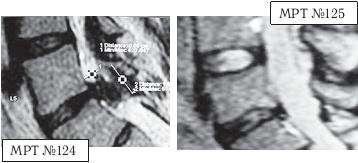

МРТ № 3

На МРТ № 3 — поясничный отдел позвоночника. (На данном «контрольном» снимке наблюдаются остаточные явления дегенеративно-дистрофического процесса в сегменте LV-SI после устранения методом вертеброревитологии секвестрированной грыжи межпозвонкового диска.)

В поясничном отделе форма позвоночного канала, создаваемая телом и дужками позвонка, вариабельна, но чаще она пятиугольная. В норме позвоночный канал в пояснично-крестцовом отделе сужен в переднезаднем диаметре на уровне LIII и LIV позвонков. Его диаметр каудально увеличивается, и поперечное сечение канала приобретает форму, близкую к треугольной, на уровне LV-SI. У женщин канал имеет тенденцию к расширению в нижней части крестцовой области. Сагиттальный диаметр значительно уменьшается от LI к LIII почти неизменен от LIII к LIV и увеличивается от LIV к LV. В норме переднезадний диаметр позвоночного канала в среднем равен 21 мм (15–25 мм).

Существует простая и удобная формула определения ширины позвоночного канала:

нормальный сагиттальный размер не менее 15 мм;

11–15 мм — относительный стеноз;

менее 10 мм — абсолютный стеноз. Уменьшение этого соотношения свидетельствует о сужении канала.

Высота поясничных межпозвонковых дисков 8–12 мм, нарастает от LI до LIV-LV, обычно уменьшается на уровне LV-SI